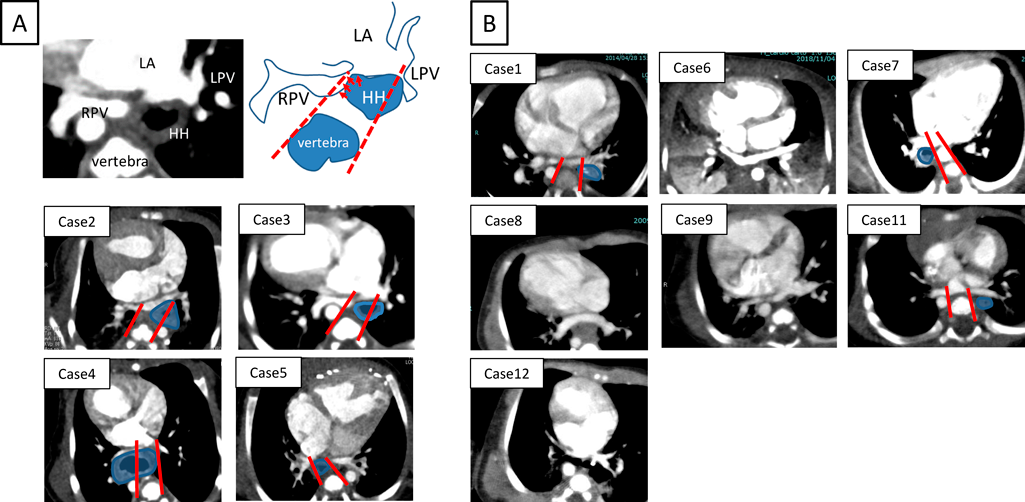

滑脱した胃と肺静脈との位置関係(Figs. 4, 5)

胸部CT画像における滑脱した胃と肺静脈との位置関係の相違を,肺静脈圧排例と非圧排例で観察し比較した.13例全例において肺静脈は共通肺静脈腔を形成し心房に接続していた.肺静脈圧排群(症例2, 3, 4, 5)では,①滑脱した胃の先進部が共通肺静脈腔と同じ高さに達している,②滑脱した胃は必ず心房椎体間に位置し,肺静脈を後方から圧排している,といった特徴を有していた.なお,下行大動脈は肺静脈圧排に関与していなかった.一方で肺静脈非圧排群では,①滑脱した胃の先進部が共通肺静脈腔の高さに達していない例(症例6, 8, 9, 12)と,②滑脱した胃の先進部が共通肺静脈腔の高さに達していても,共通肺静脈腔よりも末梢に位置している例(症例1, 7, 11)があった.肺静脈圧排群と非圧排群の特徴は,椎体の両縁から左右の肺静脈開口部へそれぞれ線を引き,その線の間に滑脱した胃が含まれるかどうかでより明確に判断できた(Fig. 4A).肺静脈圧排群では滑脱した胃は同線の間に位置した(Fig. 4A).一方で非圧排群では,滑脱した胃は同線外側に位置するか,肺静脈心房開口部とは同じCT断面で観察されず肺静脈開口部よりも腹側に位置していた(Fig. 4B).

Fig. 4 Chest CT images of all cases

If the pulmonary vein and hiatal hernia (HH) are in the same cross-section, the round shows HH (Case 1–5, 7, 11). A: In case 2–5, the pulmonary vein compression is observed. B: In case 1, 6–9, 11–12, the pulmonary vein compression is not observed.

Pediatric Cardiology and Cardiac Surgery 41(1): 42-50 (2025)

Fig. 5 The round shows hiatal hernia (HH) and the arrow shows pulmonary vein compression by HH

Case 3: With the progression of funnel chest, the pulmonary vein continues to be compressed. Case 9: Despite progression of funnel chest, there is no compression of the pulmonary veins.

また,肺静脈圧排群のうち症例3, 4, 非圧排群のうち症例8, 9, 12では経時的な漏斗胸の増悪を認めた.肺静脈圧迫群である症例3, 4は漏斗胸の進行に伴い肺静脈圧排が持続していたが,非圧排群である症例8, 9, 12は漏斗胸の増悪にもかかわらず肺静脈圧排の出現はなかった.Fig. 5に肺静脈圧排群である症例3,非圧排群である症例9の経時的変化を示す.漏斗胸は滑脱した胃による肺静脈圧排の増幅要因として影響していた.